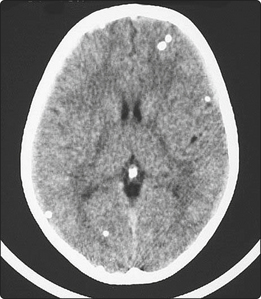

The most important human tapeworms are Taenia saginata (beef tapeworm) and Taenia solium (pork tapeworm) (Fig. 3.34.2). Humans acquire tapeworms by eating undercooked meat containing cysticerci (larval cysts in muscle), which gives the meat a ‘measly’ appearance. The cyst evaginates in the small intestines and attaches to the mucosa, where it forms proglottids and grows to an adult worm of 5–10 m in length. Infection remains asymptomatic until the mobile proglottids are passed in the stool. If humans ingest eggs of T. solium with faecally contaminated food, the larva migrates to the muscles or to the brain to encyst, causing muscle calcifications and seizures (neurocysticercosis, Fig. 3.34.3).